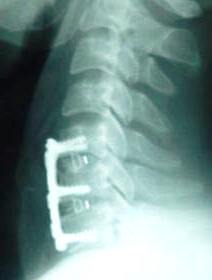

Discectomy of C5-6 and C6-7 with removal of the compressing fragments at the left foramen of C6-7. Insertion of Fidji cages 17 mm width 6.3 height and 12 mm depth was inserted to the C5-6 level with novabone. Another cage 17 mm width, 6.1 mm height and 12 mm depth was inserted with novabone to the C6-7 level. Using Trinica Zimmer miniplate 2 level 44 mm length was used to fuse C5-6-7. Image-intensifier was used at all stages of the operation.

Immediate postoperative X-ray 6 hours after surgery after ambulating.

Trinica Zimmer cervical miniplate